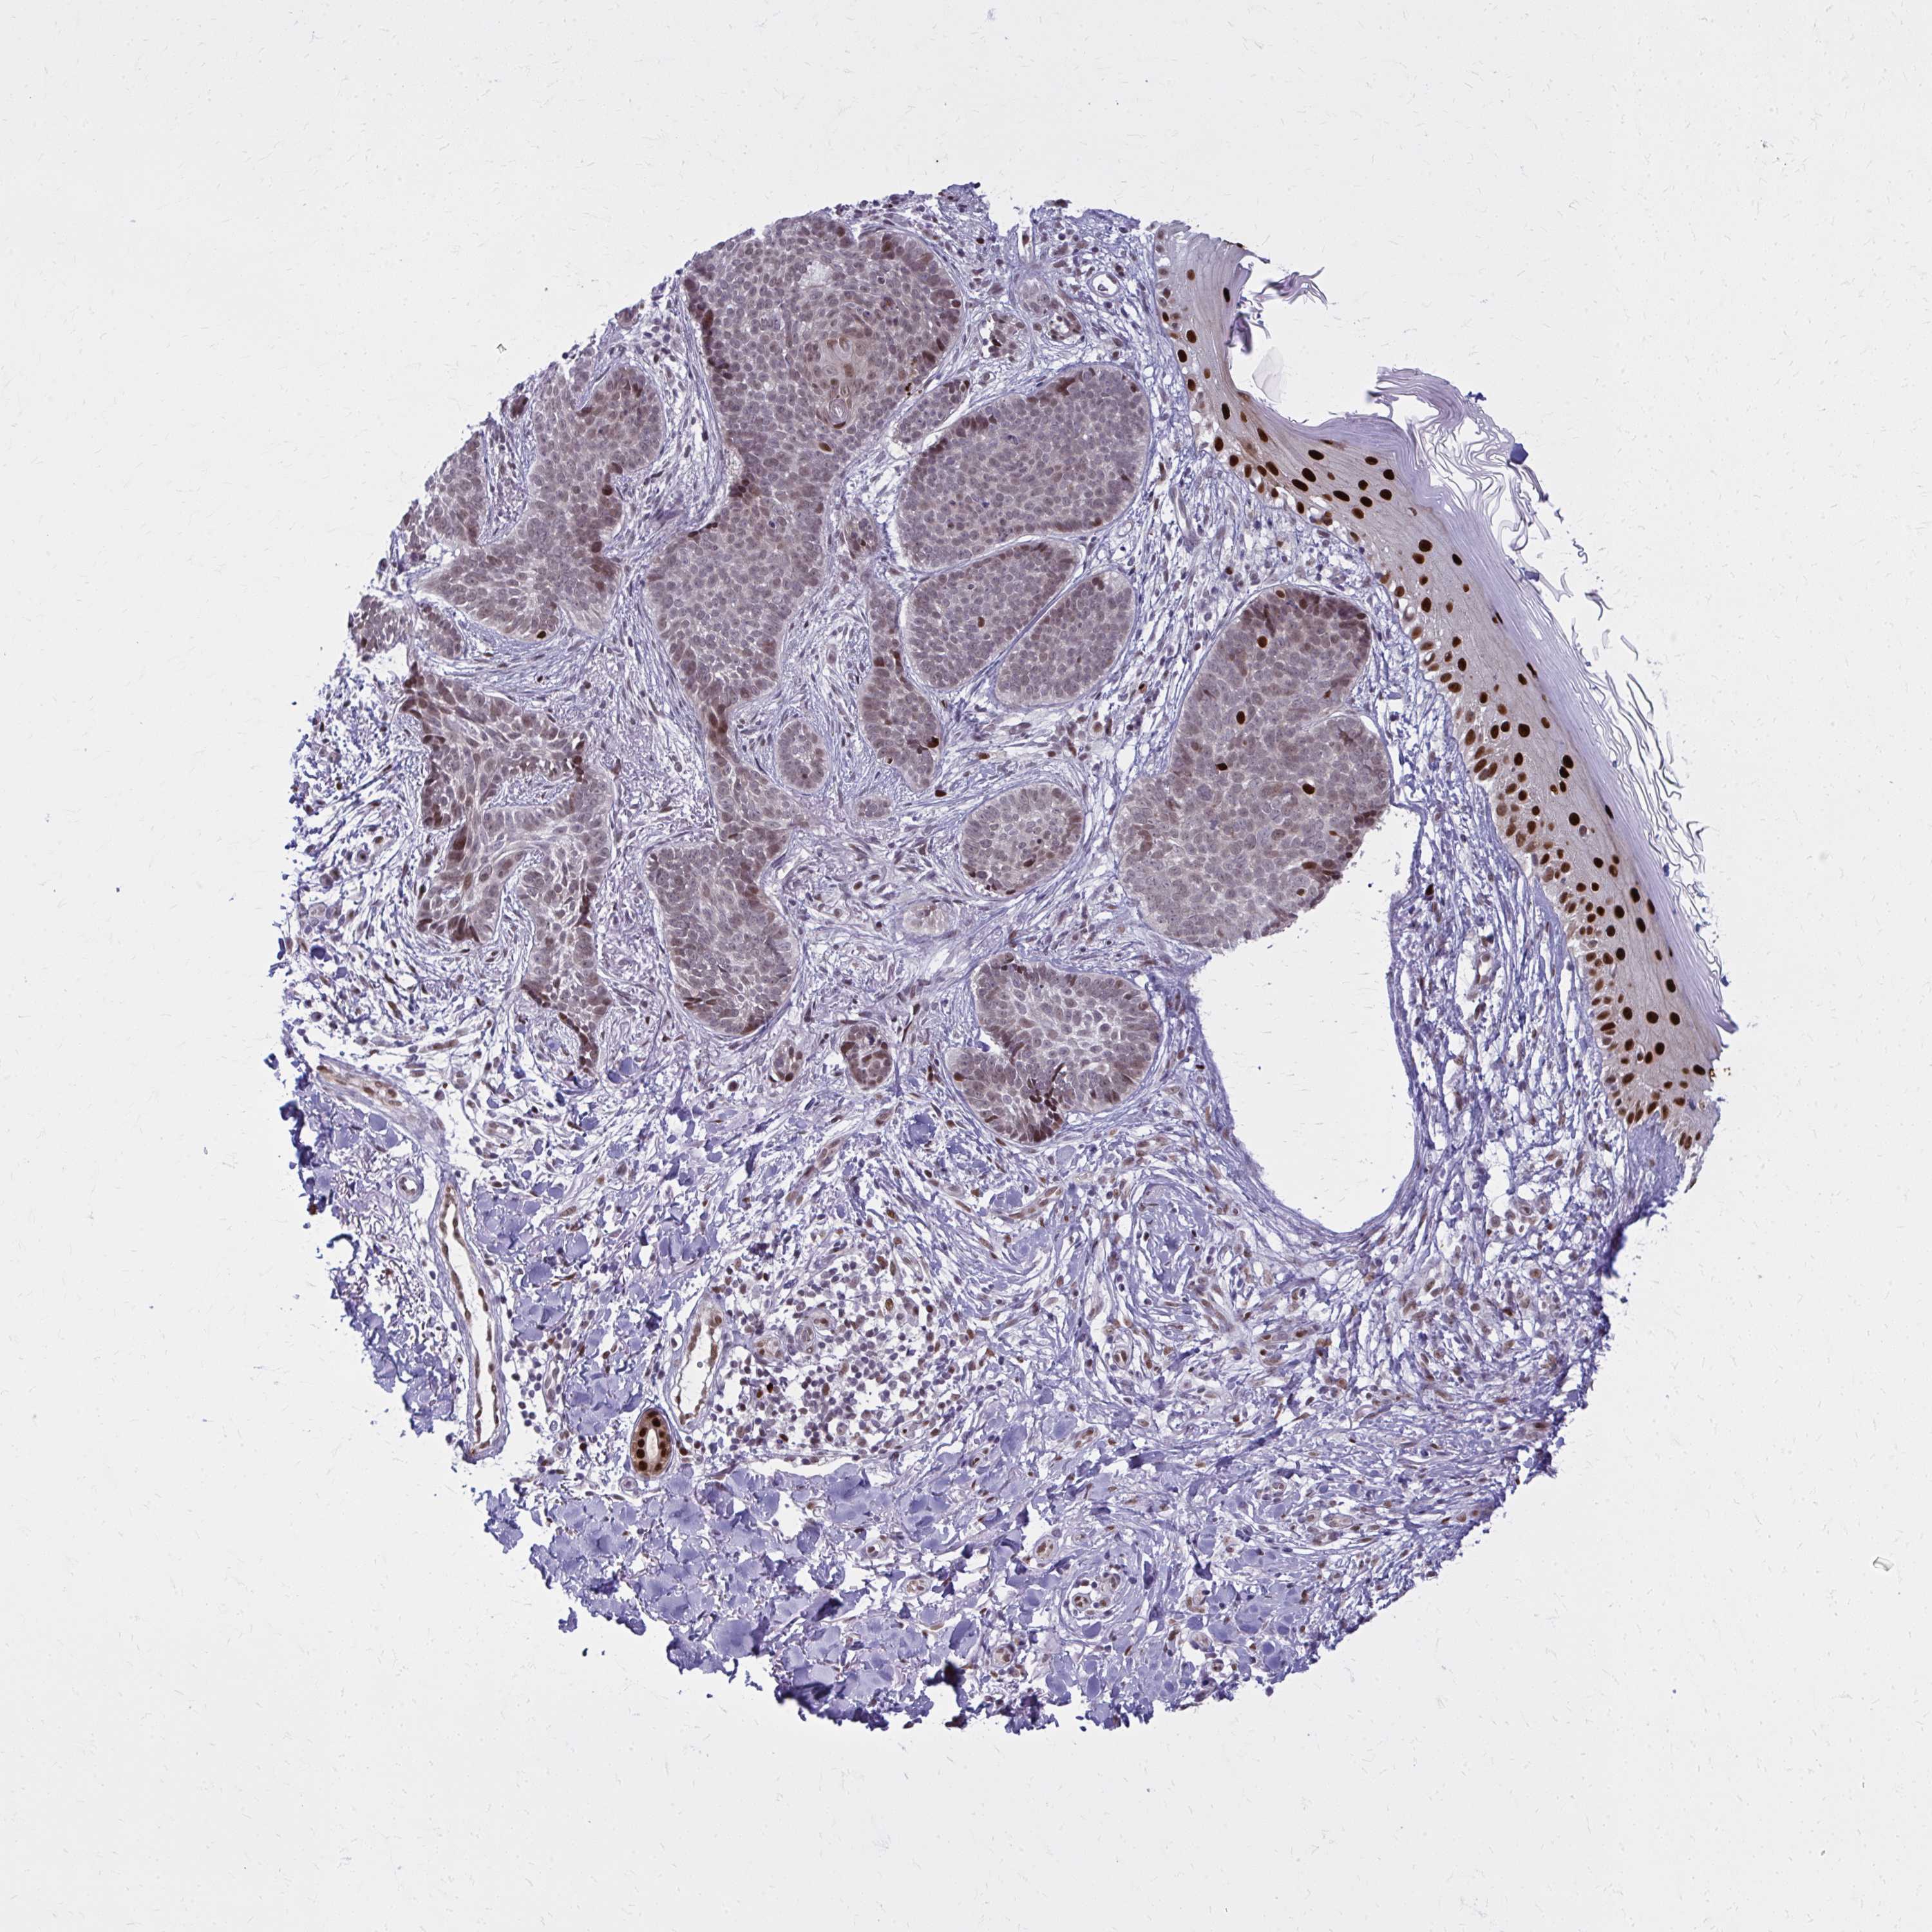

SKIN CANCER - Protein expressioni

A mouse-over function shows sample information and annotation data. Click on an image to view it in a full screen mode. Samples can be filtered based on level of antibody staining by selecting one or several of the following categories: high, medium, low and not detected. The assay and annotation is described here.

Antibody staining in the annotated cell types in the current human tissue is reported as not detected, low, medium, or high, based on conventional immunohistochemistry profiling in selected tissues. This score is based on the combination of the staining intensity and fraction of stained cells.

Each image is clickable and will lead to virtual microscopy that enables deeper exploration of all samples and also displays staining intensity scores, fraction scores and subcellular localization as well as patient and tissue information for each sample.

Antibody HPA059632

Staining

High

Intensity

Strong

Quantity

>75%

Location

Nuclear

Basal cell carcinoma

Squamous cell carcinoma, NOS